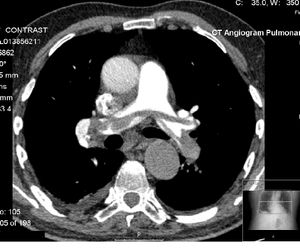

컴퓨터 단층 혈관 조영술(CTA)은 몸 전체의 동맥과 정맥을 시각화하기 위한 일종의 조영 CT이다.[47] 이는 뇌에 혈액을 공급하는 동맥부터 폐, 신장, 팔, 다리에 혈액을 공급하는 동맥까지 다양하다. 이러한 유형의 검사의 예로는 CT 폐동맥 혈관 조영술(CTPA)이 있으며, 이는 폐색전증(PE)을 진단하는 데 사용된다. 이 검사는 컴퓨터 단층 촬영과 요오드 조영제를 사용하여 폐동맥의 영상을 얻는다.[48][49][50] CT 스캔은 시술 전에 임상의에게 혈전의 위치와 수에 대한 더 많은 정보를 제공함으로써 혈관 조영술의 위험을 줄일 수 있다.[51][52]

컴퓨터 단층 혈관 조영술(CTA)은 몸 전체의 동맥과 정맥을 시각화하기 위한 일종의 조영 CT이다.[47] 이는 뇌에 혈액을 공급하는 동맥부터 폐, 신장, 팔, 다리에 혈액을 공급하는 동맥까지 다양하다. 이러한 유형의 검사의 예로는 CT 폐동맥 혈관 조영술(CTPA)이 있으며, 이는 폐색전증(PE)을 진단하는 데 사용된다. 이 검사는 컴퓨터 단층 촬영과 요오드 조영제를 사용하여 폐동맥의 영상을 얻는다.[48][49][50] CT 스캔은 시술 전에 임상의에게 혈전의 위치와 수에 대한 더 많은 정보를 제공함으로써 혈관 조영술의 위험을 줄일 수 있다.[51][52]특수한 조영 CT 촬영법은 다음과 같다.